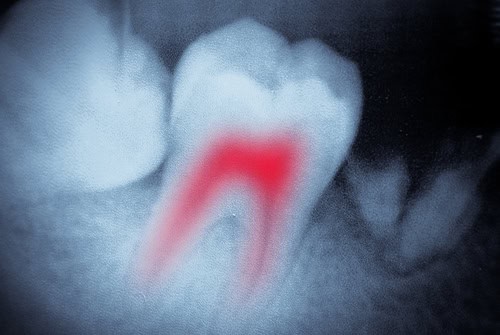

A root canal can help in many ways. When you look at your teeth, you only see the outside structure. You see the surface enamel and the hard layer of the tooth known as dentin. What you don’t see is the tooth pulp that lies within. This pulp contains blood vessels, connective tissue, and nerves.

The pulp is responsible for helping your teeth grow during development, but once the teeth are established, it is not necessary because the tooth receives nourishment from the surrounding tissue and gums.

Deep decay on the outside of a tooth can penetrate into the pulp, resulting in inflammation and infection. When this occurs, a root canal is necessary to remove the infection and the pulp. By doing this, the dentist is able to save the structural integrity of the tooth.